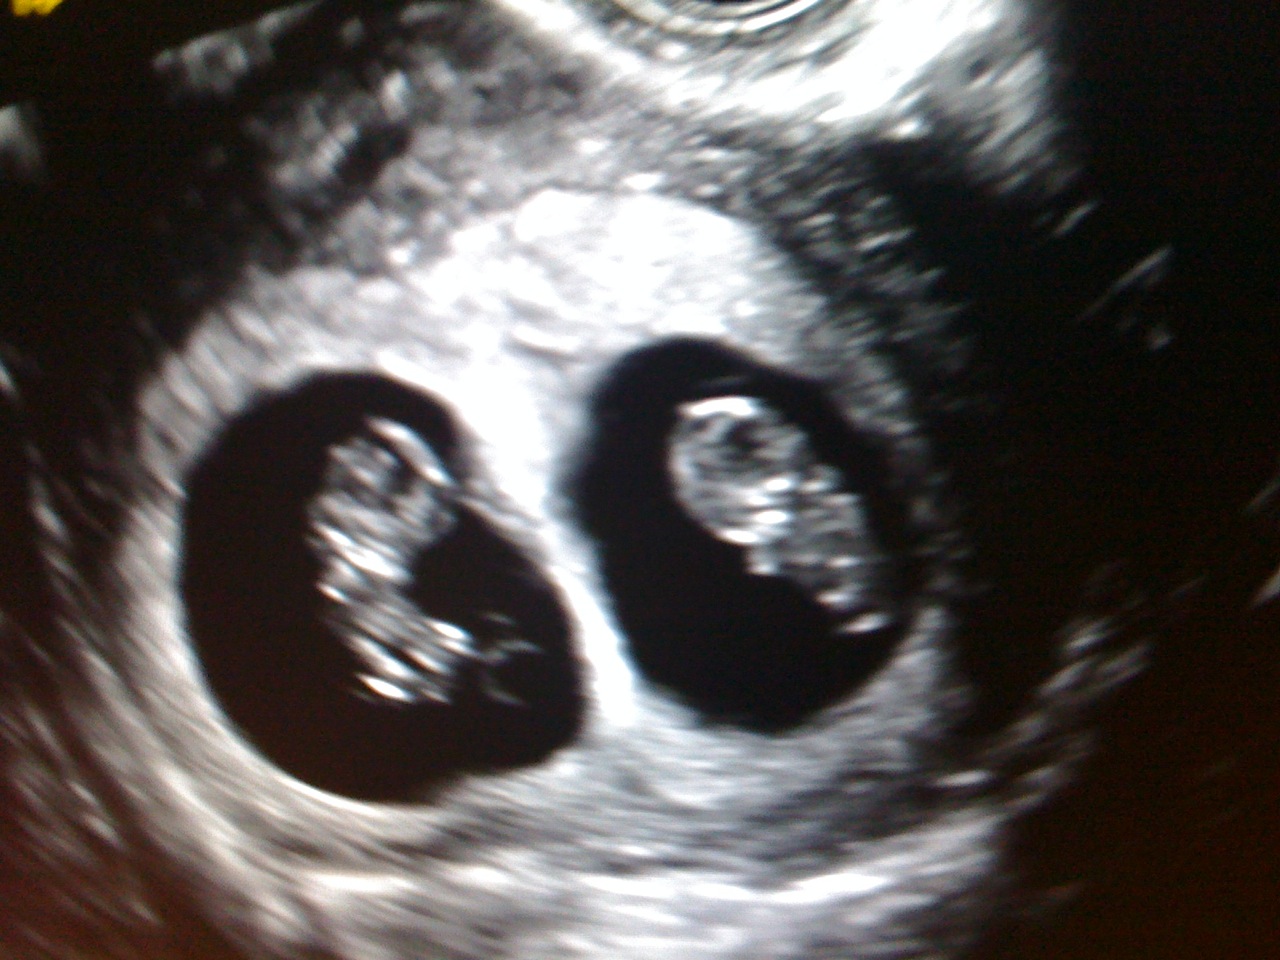

And two perfect heartbeats! Today really could not be any better of a day! I had some cramping last night which totally freaked me out but my RE reassured me that it's just my body making room for TWO perfect babies.

He said everything looks perfect. One baby is measuring 6weeks, the other is measuring 6 weeks and 1 day. We got to see and hear their heartbeats and my heart just completely melted. I could not be any happier. Brett insists that because one heartbeat was slower then the other, the one is a boy and the other is a girl. The Dr. said oh no, I say two girls! (but of course none of us really know!)

So here are our beautiful little babies...they've already grown so much from last week. Our next appointment is the 18th and I cannot wait to see how much bigger they get by then!